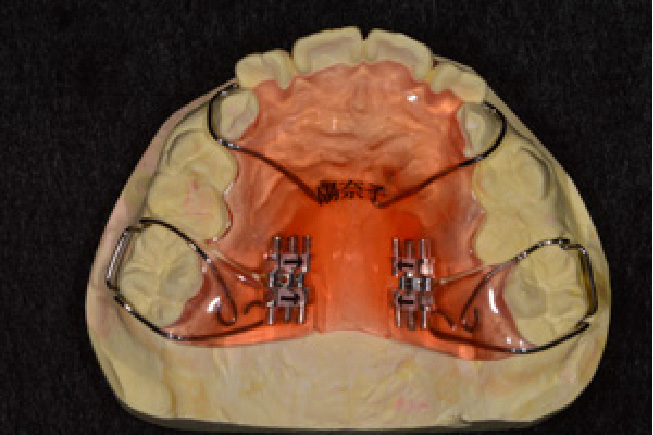

• 予防矯正

歯並びの改善や、筋機能改善(適応年齢3~17歳程度)

歯ならびだけでなく、口の周りや舌の筋肉の機能の改善。正常な成長発育を促す予防的な矯正治療。

【自費診療:プレオルソ:55,000円、交換:11,000円、 床矯正、その他装置 77,000円~】